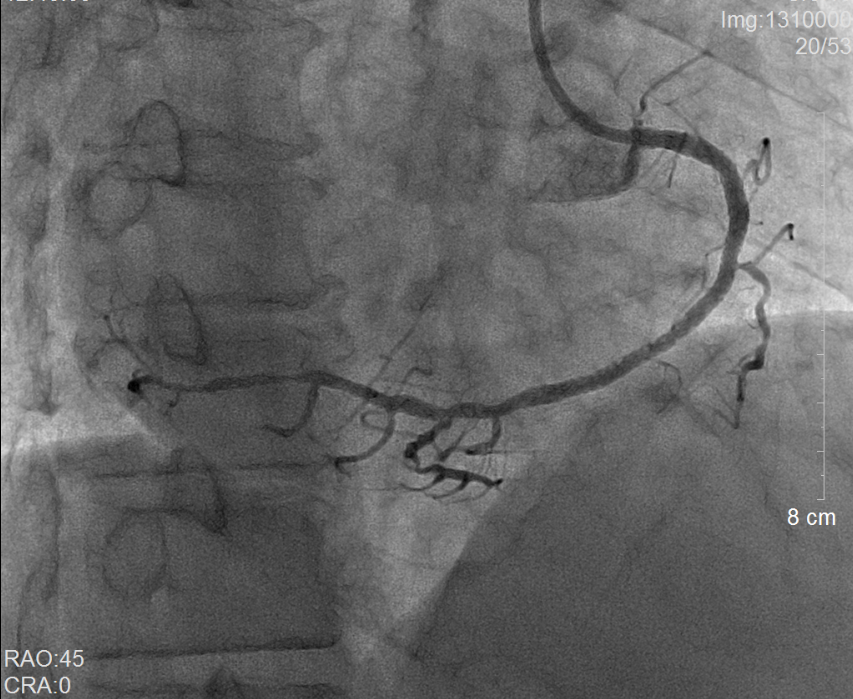

术前冠脉造影提示右冠状动脉弥漫性病变                 术后冠脉造影提示右冠状动脉血流通畅

当地县医院立即通过胸痛中心急救系统向我院心内科发出求助。当日二线值班的副主任医师谢泓及住院总医师李爱娜了解情况后当即决定将患者转入我院,备行急诊经皮冠状动脉介入治疗(PCI)。而值急诊介入班的彭峰副主任医师和蔡瀚医师得知消息后也立即赶往待命。风驰电掣的120急救车一到达医院后,接诊医生立即将林先生送往介入手术室。不料,术中冠脉造影提示林先生为极其罕见的“右位心合并急性心肌梗死”,这无疑大大增加了手术的操作难度。凭借心内科介入组医护人员平日的训练有素和娴熟配合,很快就为林先生开通了“犯罪血管”——右冠状动脉,从进入医院大门至球囊打通血管的时间(D-to-B)仅仅60分钟(国际标准为<90分钟)。